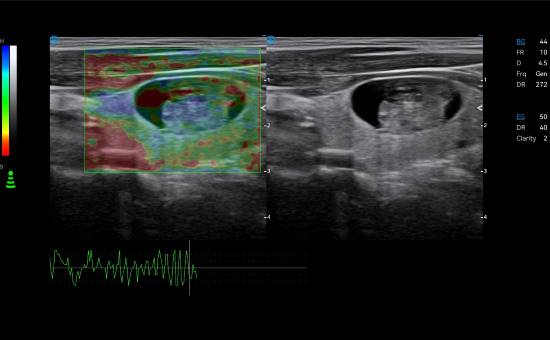

Contrast Harmonic Imaging

The blood flow perfusion status can be visualized in real time with contrast agent for efficient analysis of tumors in liver, thyroid and other organs. The timer function further enhances the diagnostic accuracy.